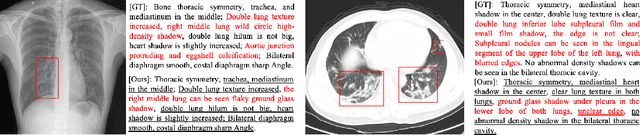

Abstract:Medical imaging technologies, including computed tomography (CT) or chest X-Ray (CXR), are largely employed to facilitate the diagnosis of the COVID-19. Since manual report writing is usually too time-consuming, a more intelligent auxiliary medical system that could generate medical reports automatically and immediately is urgently needed. In this article, we propose to use the medical visual language BERT (Medical-VLBERT) model to identify the abnormality on the COVID-19 scans and generate the medical report automatically based on the detected lesion regions. To produce more accurate medical reports and minimize the visual-and-linguistic differences, this model adopts an alternate learning strategy with two procedures that are knowledge pretraining and transferring. To be more precise, the knowledge pretraining procedure is to memorize the knowledge from medical texts, while the transferring procedure is to utilize the acquired knowledge for professional medical sentences generations through observations of medical images. In practice, for automatic medical report generation on the COVID-19 cases, we constructed a dataset of 368 medical findings in Chinese and 1104 chest CT scans from The First Affiliated Hospital of Jinan University, Guangzhou, China, and The Fifth Affiliated Hospital of Sun Yat-sen University, Zhuhai, China. Besides, to alleviate the insufficiency of the COVID-19 training samples, our model was first trained on the large-scale Chinese CX-CHR dataset and then transferred to the COVID-19 CT dataset for further fine-tuning. The experimental results showed that Medical-VLBERT achieved state-of-the-art performances on terminology prediction and report generation with the Chinese COVID-19 CT dataset and the CX-CHR dataset. The Chinese COVID-19 CT dataset is available at https://covid19ct.github.io/.